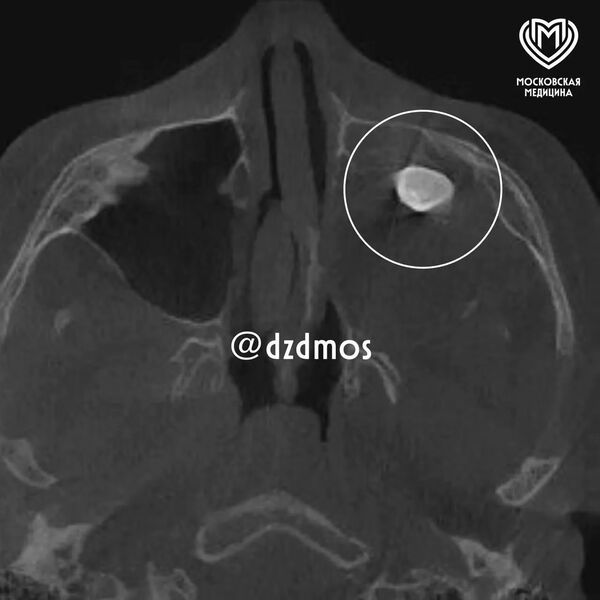

Врачи Филатовской больницы в Москве удалили подростку зуб, который вырос в носу. Об этом сообщает столичный депздрав в своем канале в Max.

Уточняется, что 15-летний мальчик попал в больницу с жалобами на асимметрию лица и заложенность носа. До этого, как отметили в депздраве, мальчика осматривали врачи частной клиники — они нашли в гайморовой пазухе сформировавшийся зуб и предложили удалить его.

Родители подростка решили выслушать второе мнение и обратились за консультацией в Филатовскую больницу, где по результатам консилиума врачи предложили провести операцию по Колдуэллу-Люку, то есть обеспечить доступ через верхнюю десну, чтобы вернуть ему возможность нормально дышать.

Сделав разрез, врачи обнаружили новообразование, внутри которого и находился зуб, рассказал хирург-оториноларинголог Вугар Достиев. По его словам, доброкачественная опухоль оказалась тератомой — эмбрионально-клеточным новообразованием, внутри которого могут находиться элементы тканей, несвойственные этому участку тела.

Достиев уточнил, что после восстановления функций подростка выписали с хорошим самочувствием, также постепенно асимметрия его лица и заложенность носа полностью исчезли.